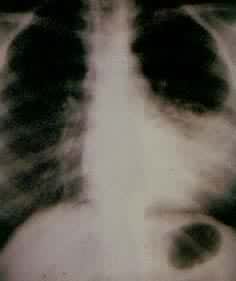

肺部疾病(一) 肺部疾病(二) 大叶肺炎 小叶肺炎 间质性肺炎 肺脓肿(正位) 肺脓肿(侧位) 支气管扩张 浸润性肺结核

肺结核空洞 肺不张